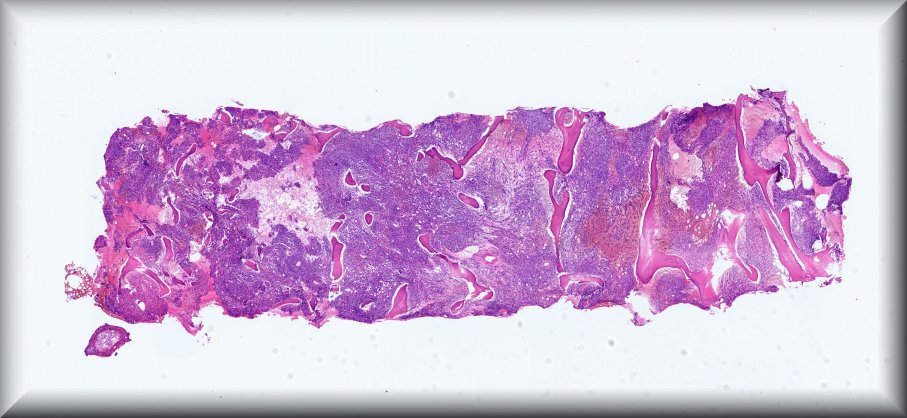

Caso 2.- Roger Eduardo Casco Zuniga; Evelyn Beatriz Troncoso Hernández; Svetlana Shalygina; Paola Andrea Chilito Paredes; José Luis Losa García.

Hospital General Universitario de Alicante.

Varón de 79 años, con antecedente de mieloma múltiple en actual tratamiento. Acude a servicio de urgencias por astenia de 4 días de evolución y presencia de pancitopenias persistente a pesar de tratamiento. Se realiza biopsia de médula ósea en el que se observa infiltración difusa por células pequeñas de estirpe linfoide y un 15% aproximado de células plasmáticas con restricción de cadenas ligeras Kappa.